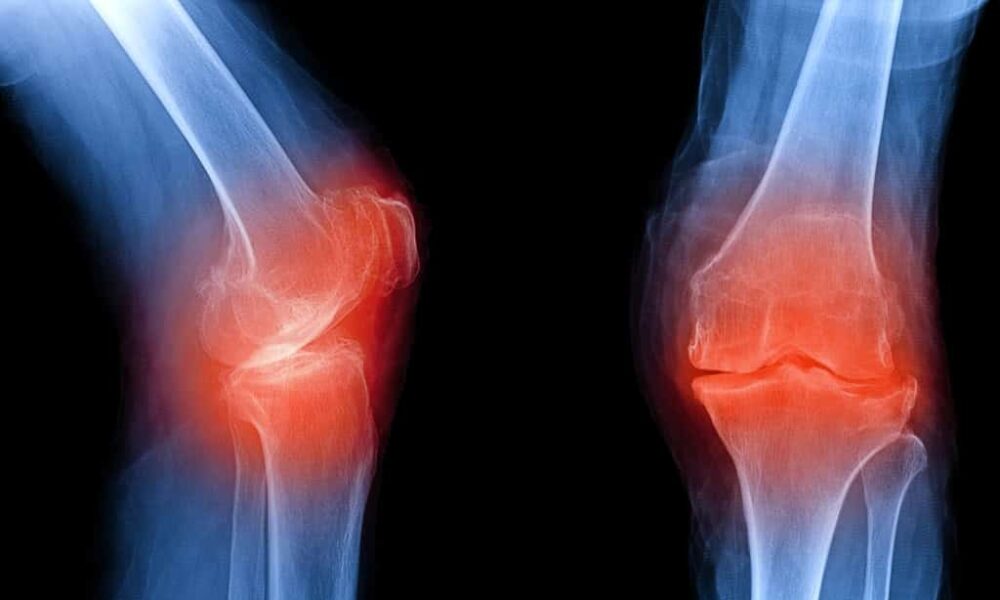

[/quote]Η έναρξη της θεραπείας, σύμφωνα με τον Βασίλειο Χατζηλουλούδη, Ρευματολόγο, αναπλ. Γεν. Γραμματέα του Ελληνικού Ιδρύματος Ρευματολογίας, 12 εβδομάδες μετά την εμφάνιση των συμπτωμάτων, μπορεί να ελαχιστοποιήσει περαιτέρω βλάβες στις αρθρώσεις και να αυξήσει την πιθανότητα ύφεσης. Δυστυχώς, όμως, τα Ρευματικά Νοσήματα διαγιγνώσκονται καθυστερημένα ή δεν διαγιγνώσκονται καθόλου. Εάν δεν ληφθεί η κατάλληλη θεραπεία, οι καθημερινές δραστηριότητες θα επηρεαστούν – μειώνοντας την ποιότητα ζωής και αυτό θα έχει αντίκτυπο στις σωματικές ικανότητες.

Οι ρευματικές παθήσεις αποτελούν το σημαντικότερο πρόβλημα υγείας στον εργαζόμενο πληθυσμό (δηλαδή στα άτομα 19-65 ετών) διότι είναι το συχνότερο αίτιο χρόνιου προβλήματος υγείας, μακροχρόνιας σωματικής ανικανότητας, απουσίας από την εργασία και ιατρικών επισκέψεων. Το μέγεθος του προβλήματος των ρευματικών παθήσεων καθορίζεται από την συχνότητα στον γενικό πληθυσμό και τις επιπτώσεις στους ίδιους τους ασθενείς, στο κοινωνικό σύνολο, στο σύστημα υγείας και στην εθνική οικονομία. Τα ανωτέρω στοιχεία προέρχονται από την πανελλήνια επιδημιολογική έρευνα του Ελληνικού Ιδρύματος Ρευματολογίας, που αναδεικνύει την αναγκαιότητα της σωστής πληροφόρησης και της έγκαιρης διάγνωσης των ρευματικών παθήσεων.